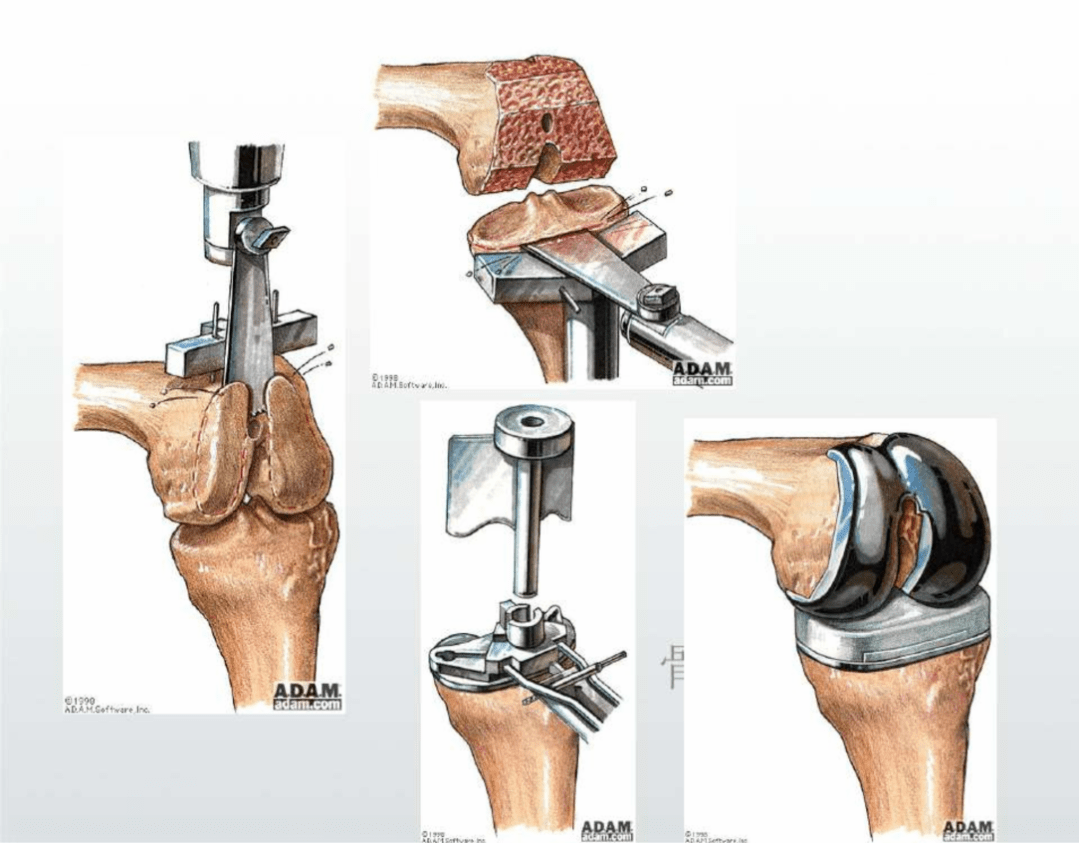

人工膝關(guān)節(jié)置換:是在近代人工髖關(guān)節(jié)成功應(yīng)用于病人后逐漸發(fā)展起來(lái)的一種治療膝關(guān)節(jié)疾病的新技術(shù),是治療嚴(yán)重膝骨關(guān)節(jié)病的切實(shí)有效方法,它能非常有效地根除晚期膝關(guān)節(jié)病痛,極大地提高病人的生活質(zhì)量,在發(fā)達(dá)國(guó)家比較流行。膝關(guān)節(jié)置換就是切除膝關(guān)節(jié)軟骨損壞的表面,并安置一個(gè)人工表面和墊片,構(gòu)成一個(gè)新的關(guān)節(jié),該手術(shù)可以減少患者的疼痛,糾正患者膝關(guān)節(jié)的畸形,恢復(fù)患者膝關(guān)節(jié)的屈伸活動(dòng)。

人工膝關(guān)節(jié)置換術(shù)適合什么樣患者:老年退變性膝關(guān)節(jié)骨性關(guān)節(jié)炎:其癥狀已明顯影響關(guān)節(jié)活動(dòng)和生活能力,經(jīng)保守治療不能改善癥狀者;適用于類(lèi)風(fēng)濕關(guān)節(jié)炎和強(qiáng)直性脊柱炎的膝關(guān)節(jié)晚期病變者;其他非感染性關(guān)節(jié)炎引起的膝關(guān)節(jié)病損并伴有疼痛和功能障礙者,如大骨節(jié)病、血友病性關(guān)節(jié)炎等;創(chuàng)傷性骨性關(guān)節(jié)炎:如粉碎性脛骨平臺(tái)骨折后關(guān)節(jié)面未能修復(fù)而嚴(yán)重影響功能的,因半月板損傷或切除后導(dǎo)致的繼發(fā)性骨關(guān)節(jié)炎等疾??;大面積的膝關(guān)節(jié)骨軟骨壞死或其他病變不能通過(guò)常規(guī)手術(shù)方法修復(fù)者;涉及膝關(guān)節(jié)面的腫瘤切除后無(wú)法獲得良好關(guān)節(jié)功能重建者。什么年齡適合人工膝關(guān)節(jié)置換:膝關(guān)節(jié)置換術(shù)屬于擇期手術(shù),一般適用于50-85歲的人群,最常見(jiàn)的是在60-75歲之間,只要滿足該術(shù)的適應(yīng)癥,同時(shí)保守治療無(wú)效,均可考慮做膝關(guān)節(jié)置換術(shù)。手術(shù)后1-3天可下床活動(dòng),在醫(yī)生指導(dǎo)下盡早進(jìn)行膝關(guān)節(jié)的康復(fù)訓(xùn)練,術(shù)后14天拆線。人工膝關(guān)節(jié)置換術(shù)的使用壽命:雖然人工關(guān)節(jié)假體有一定的使用壽命,到時(shí)可能會(huì)因磨損、松動(dòng)等原因需要翻修,但隨著手術(shù)技術(shù)的不斷提高以及假體材料的不斷進(jìn)步,現(xiàn)代人工關(guān)節(jié)假體的使用壽命正在不斷延長(zhǎng)。